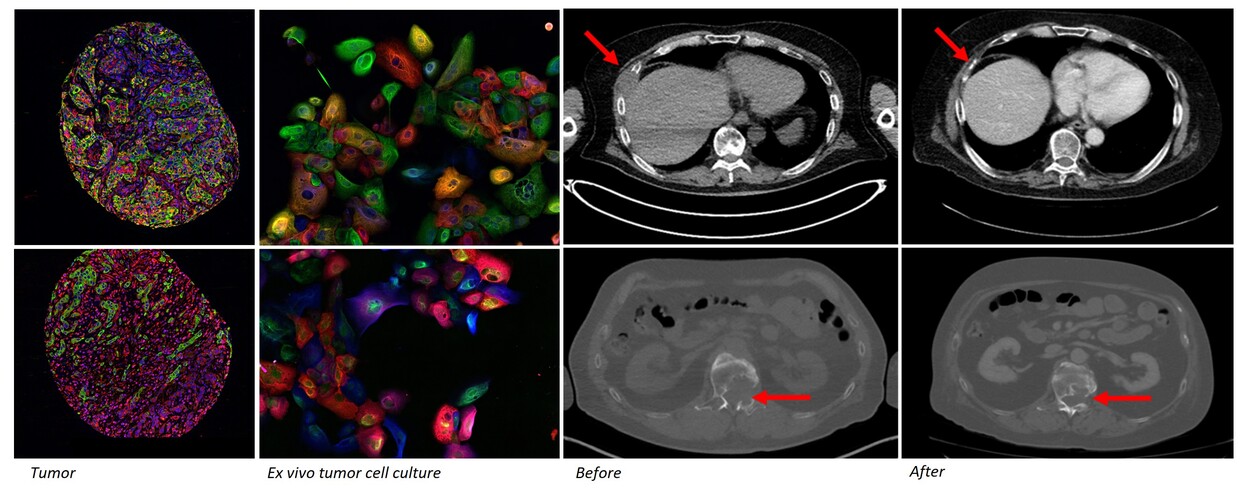

Patient derived functional tumor models retain the cellular composition and differentiation state heterogeneity of the parental tumors. Primary ex vivo models also reflect the pathology and clinical behavior of the cancer. Misvik´s ex vivo tumor models are a continuously expanding collection of early passage patient derived functional tumor models cryopreserved following initial tissue dissociation and establishment of organoid culture. The ex vivo model collection currently contains 700+ tumor samples representing 90+ different solid cancer types including rare to ultra rare cancers. The sample series also contains matched longitudinal samples from the same patient prior and after treatment allowing study of therapy efficacy in treatment naive and relapsed tumor models. All samples are incorporated on Misvik´s master RPPA (reverse-phase-protein array) sample repository for rapid target evaluation and general protein expression analysis across different cancers types.

Biologically relevant ex vivo tumor models are primary cultures isolated directly from dissociated tumor samples